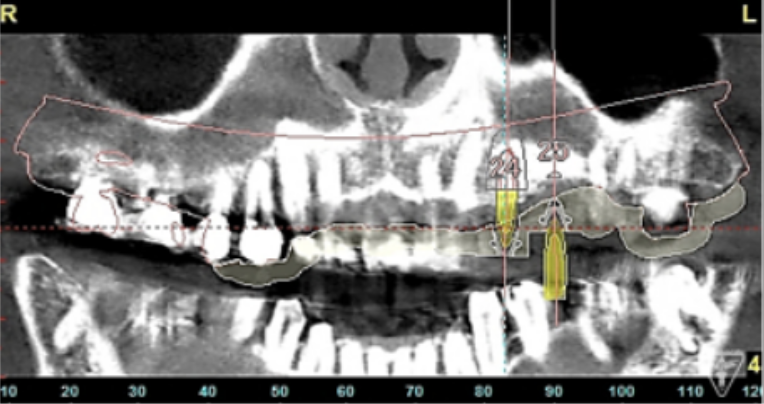

サージカルガイドの作成

インプラント埋入前のCTによる確認